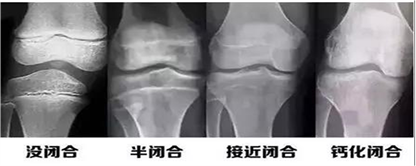

孩子一般几岁停止长高?怎样才能知道孩子还能不能再长高?

一般来说,女孩15岁、男孩16岁左右,骨骶就已经接近或达到闭合状态,身高也就失去了线性增长(即长个)的空间。女孩子13岁的骨龄,生长潜力大概4cm左右,男孩15岁的骨龄,生长潜力大概只有3cm。有些性早熟的孩子,骨骷会提前闭合,可能在12-13岁甚至更早就失去线性增长的空间。建议青春期的孩子半年监测一次骨龄,避免骨骷提前闭合,造成身高上的终生遗憾

骨龄一旦成熟,骨闭合,孩子也就失去长高的机会了,在我们门诊经常遇到这种情况,15、6岁的孩子,家长过来说,“医生,我家孩子最近两年长的不多了,我们想来测个骨龄”,拍片一看,骨骺基本要闭合了,很遗憾,孩子的身高也就快要达到终身高了。因此骨龄监测是科学身高管理过程中的必做检查项目之一。一般我们是拍左手腕骨的片子,拍片子的时候要按照工作人员的要求,摆好手的位置。对于较大年龄的孩子,家长又对身高的要求比较高的,我们可能还会加拍腿部长骨的一些片子,来全面评估,这个孩子的生长潜力。